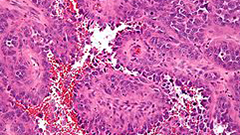

צילום מיקרוסקופי של סרטן ראשוני מסוג אנגיוסרקומה